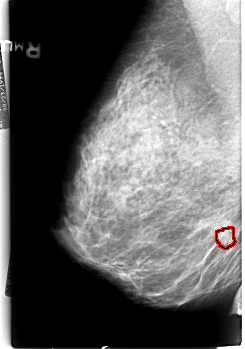

B_3009_1.RIGHT_MLO

RIGHT_MLO LINES 4528 PIXELS_PER_LINE 3176 BITS_PER_PIXEL 12 RESOLUTION 50 OVERLAY

FILE: B_3009_1.RIGHT_MLO.OVERLAY

TOTAL_ABNORMALITIES 1

ABNORMALITY 1

LESION_TYPE CALCIFICATION TYPE PLEOMORPHIC DISTRIBUTION CLUSTERED

ASSESSMENT 4

SUBTLETY 3

PATHOLOGY MALIGNANT

TOTAL_OUTLINES 1

BOUNDARY